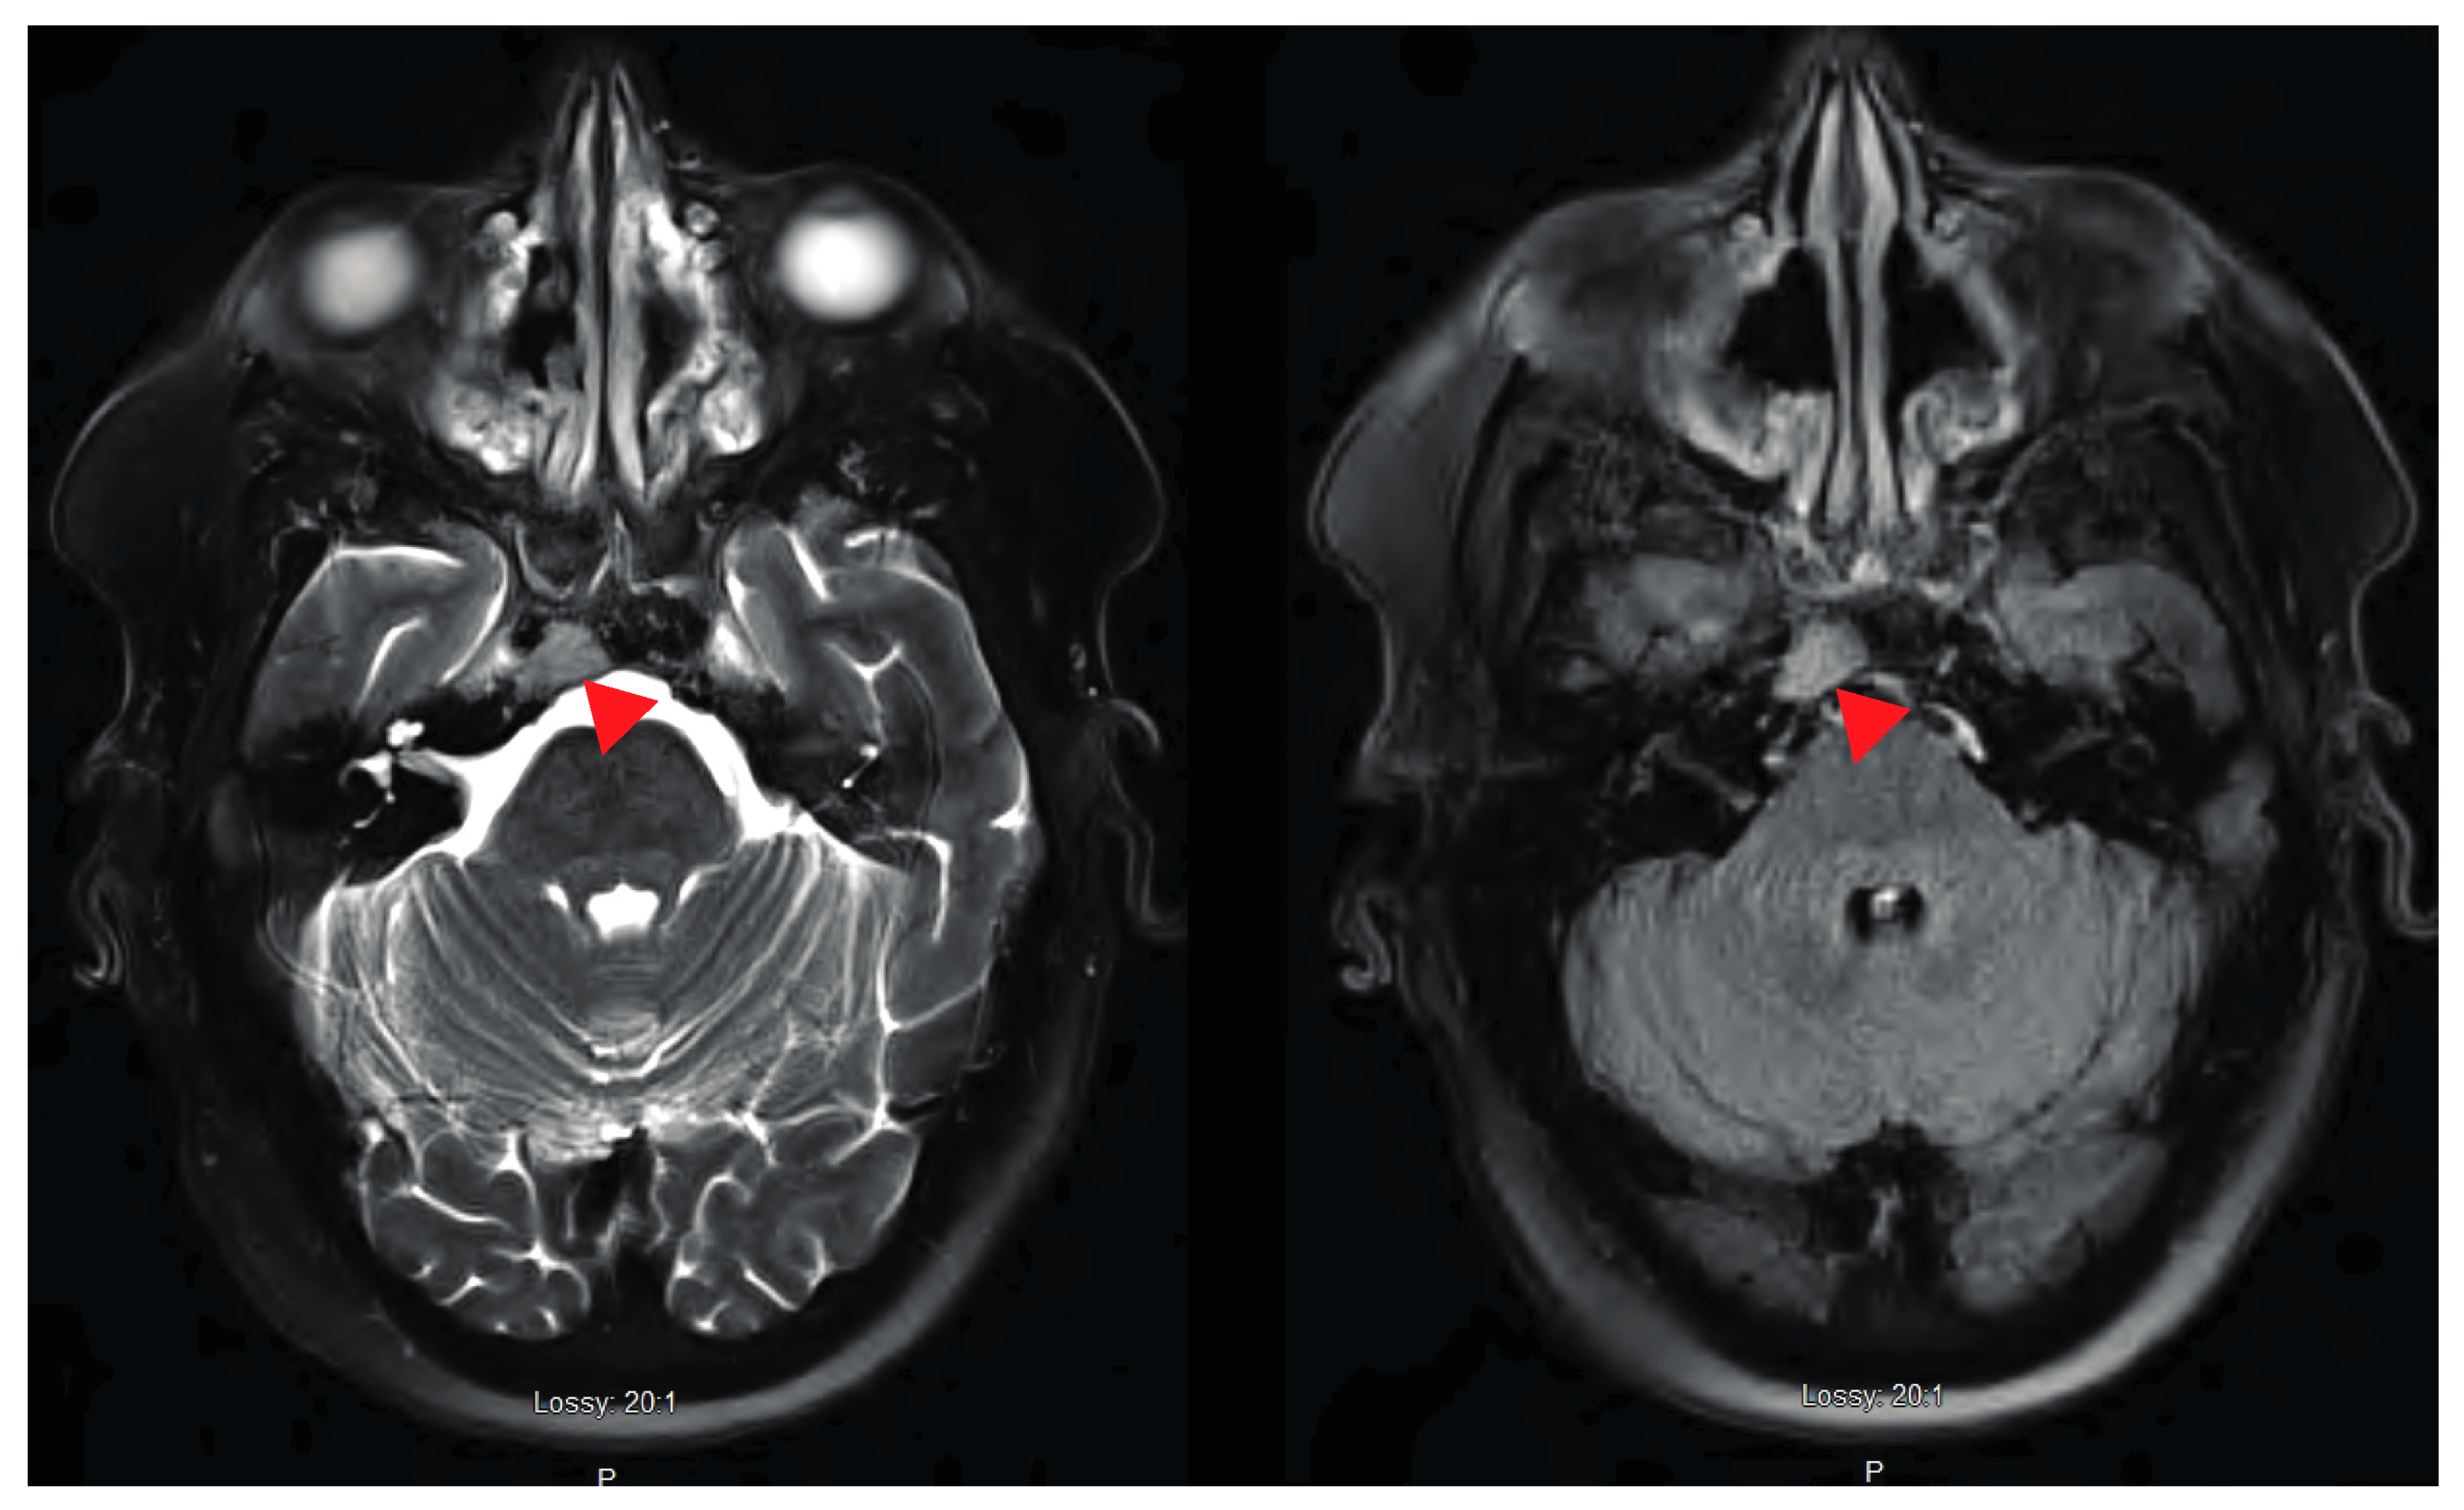

Abducens Nerve Palsy as Initial Presentation of Multiple Myeloma and Intracranial Plasmacytoma

2. Case Presentation